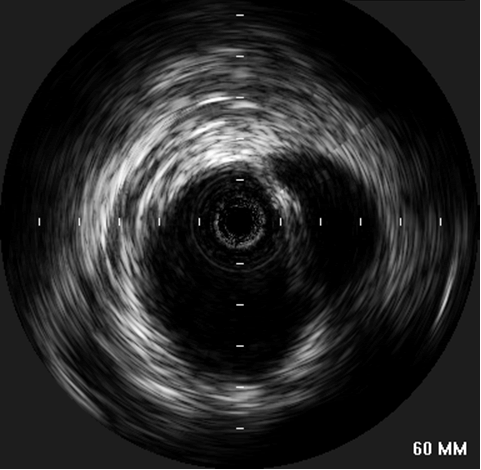

Informed consent was obtained and the patient was offered endovascular repair of the contained aortic rupture using the Medtronic Talent endoprosthesis through a single institution Investigator Investigational Device Exemption (IDE) approved by the FDA. In the endovascular suite, the patient was placed in supine position and underwent local anesthesia with sedation. The left common femoral artery was exposed and then accessed using an 18-gauge needle and a 0.035 inch flexible-tipped Bentson Starter guidewire was passed in a retrograde fashion into the descending aorta under fluoroscopic guidance. 3000U of Heparin was administered and a 14-Fr introducer sheath was placed in the left common femoral artery. The IVUS (Volcano Visions, PV 8.2 F) catheter was used to guide and advance the Starter guidewire safely across the contained rupture area into ascending aorta. Upon advancement of the IVUS probe into the thoracic aorta, the area of transection was encountered. There was a dissection flap with a dilated and disrupted area in the middle of aorta

| Figure 3: IVUS showing the site of aortic rupture. |

(Figure 3). The proximal aspect of the transection was 1.5 cm below the origin of the left subclavian artery. Origins of the arch vessels were marked on the masked picture on the fluoroscopy monitor. Using the IVUS, the aortic diameter was measured 28 mm just distal to the left subclavian artery and 29 mm at origin of the left common carotid artery. It was decided to cover the left subclavian artery to get an adequate landing zone for the endoprosthesis. Therefore, the IVUS was placed just distal to the left carotid artery and its position marked on the fluoroscopic screen. The catheter was then withdrawn until above, and then below the transected area. These measured 36 mm and 76 mm in length, respectively. With these measurements in mind, a 30 mm diameter by 130 mm in length Medtronic Talent device with 15 mm proximal wire configuration was selected to exclude the transected portion of the aorta.